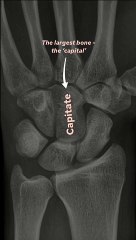

\rbr3D anatomy tutorial on the bones and joints of the hand and wrist using the BioDigital Human Browser (). This tutorial covers the basics of the bones of the hand and the names of the joints between the different bones.